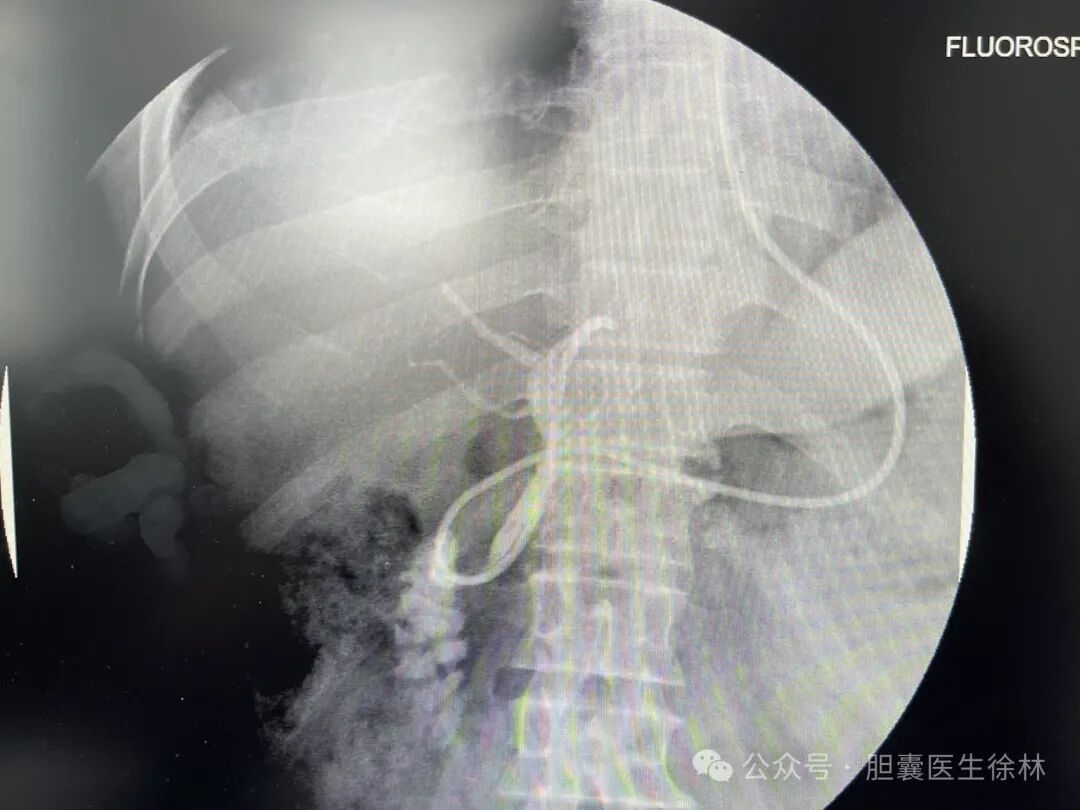

我们跟病人讲明了他的病情,采用“内镜+腔镜”的微创手术彻底清除了大叔的